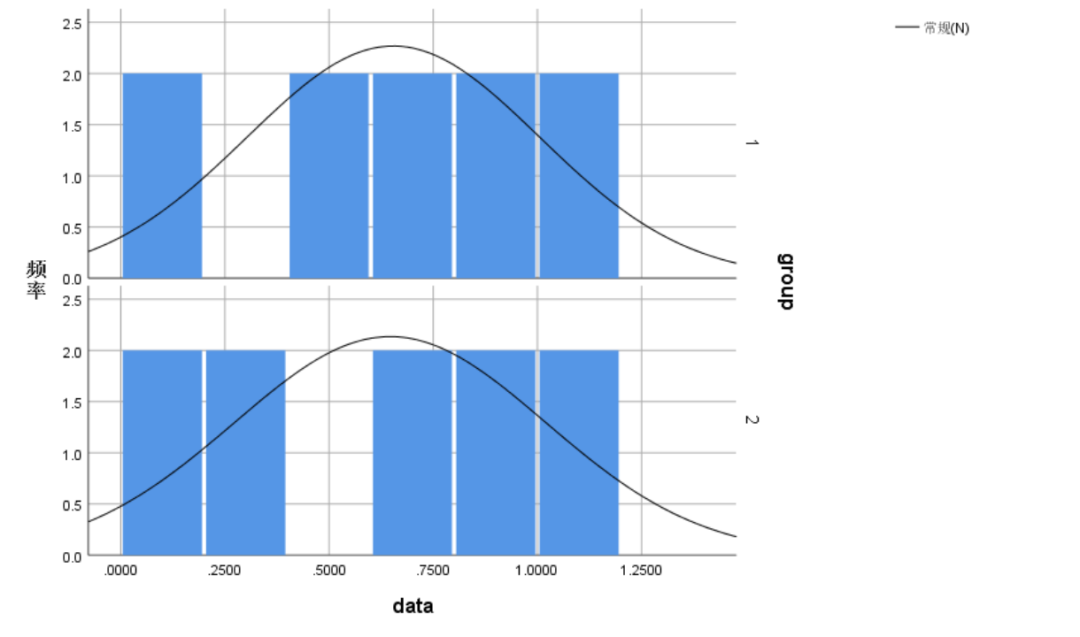

使用 Mann-Whitney U 检验判断手动测量与自动测量水平是否有差异。根据直方图判断两组测量结果分布的形状基本一致。人工测量的中位数为0.714,自动测量的中位数为0.740。Mann-Whitney U 检验结果显示,人工测量与自动测量差异无统计学意义(U=48.000,P=0.912)。